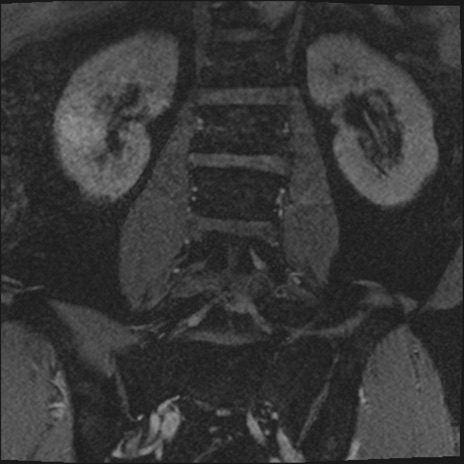

【整形】TIPS症例2 腰椎MRI 3D(冠状断像)

【症例】70歳代男性

【主訴】左下肢痛

【現病歴】2週間前くらいから腰痛、左下肢痛あり。左臀部から大腿、下腿外側のしびれが常時ある。歩行とともに同部位の痛みあり。

【身体所見】Lasegue70-/60+、Bragard-/±、PTR ±/±、ATR -/-、IP 5/5、TA 5/4、TS 5/5、EHL 右第1足趾なし/3、FHL 5/5、hypersthesia(-)、足背動脈触知良好

異常所見と診断は?